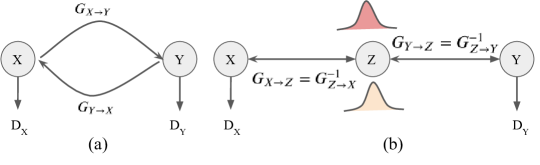

Fig. 1 illustrates the difference between cycleGAN and alignflow methods. Unlikes cycleGAN, the alignflow method is the full invertible architecture that guarantees the cycle-consistency translations between two unpaired domains without an additional function.